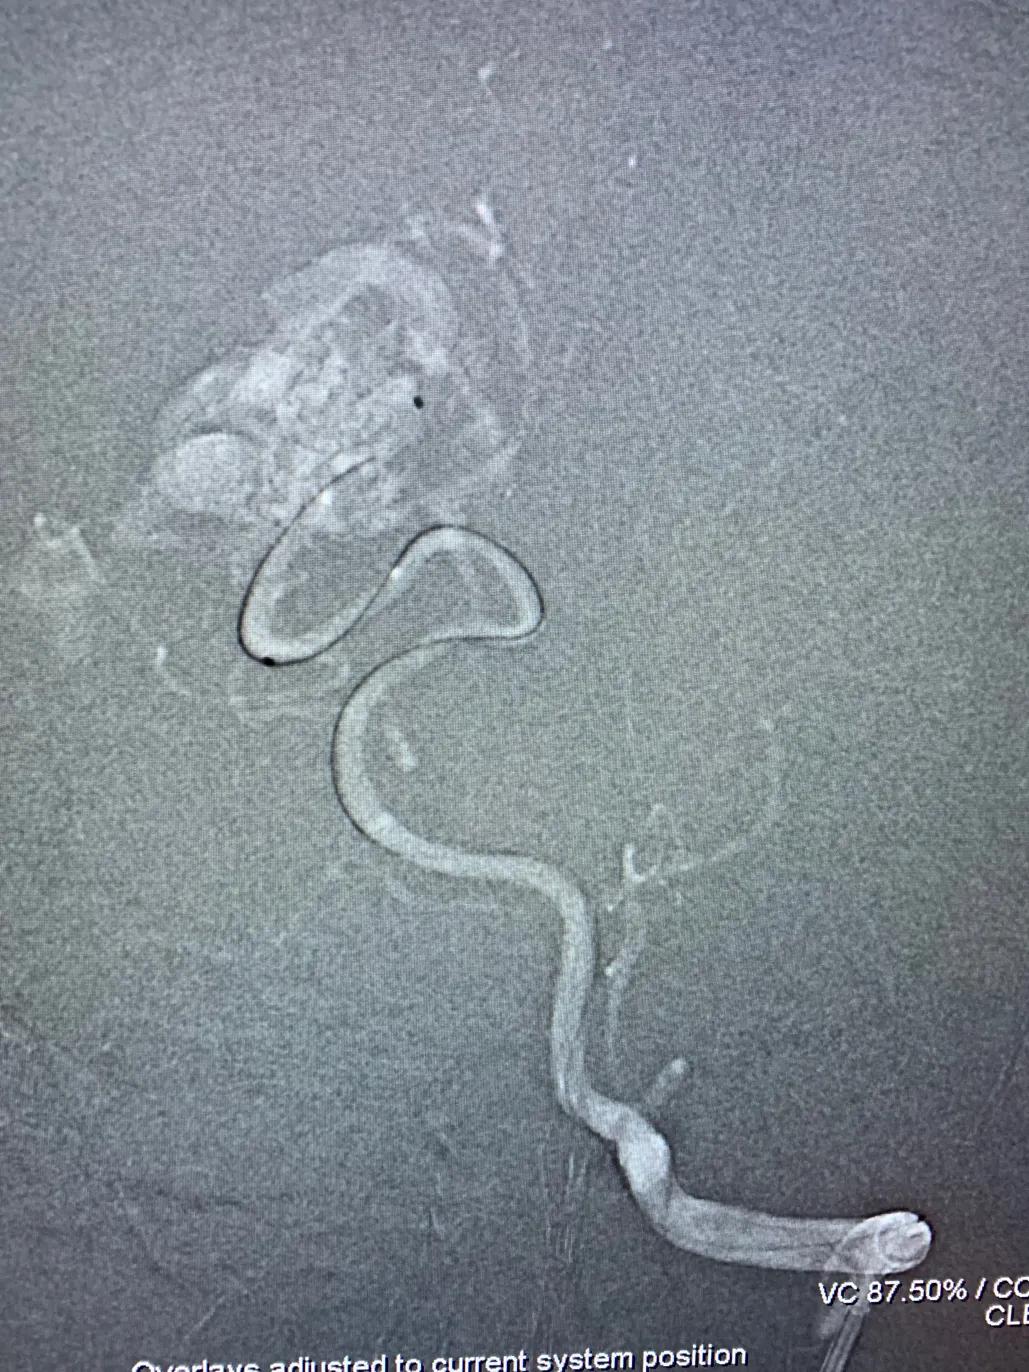

本组部分病例在使用Apollo微导管进行Onyx栓塞时,采用此种技术,可有效的阻止Onyx返流。本病例为一小女孩,右侧枕叶血管畸形,主要供血动脉为右侧大脑后动脉。